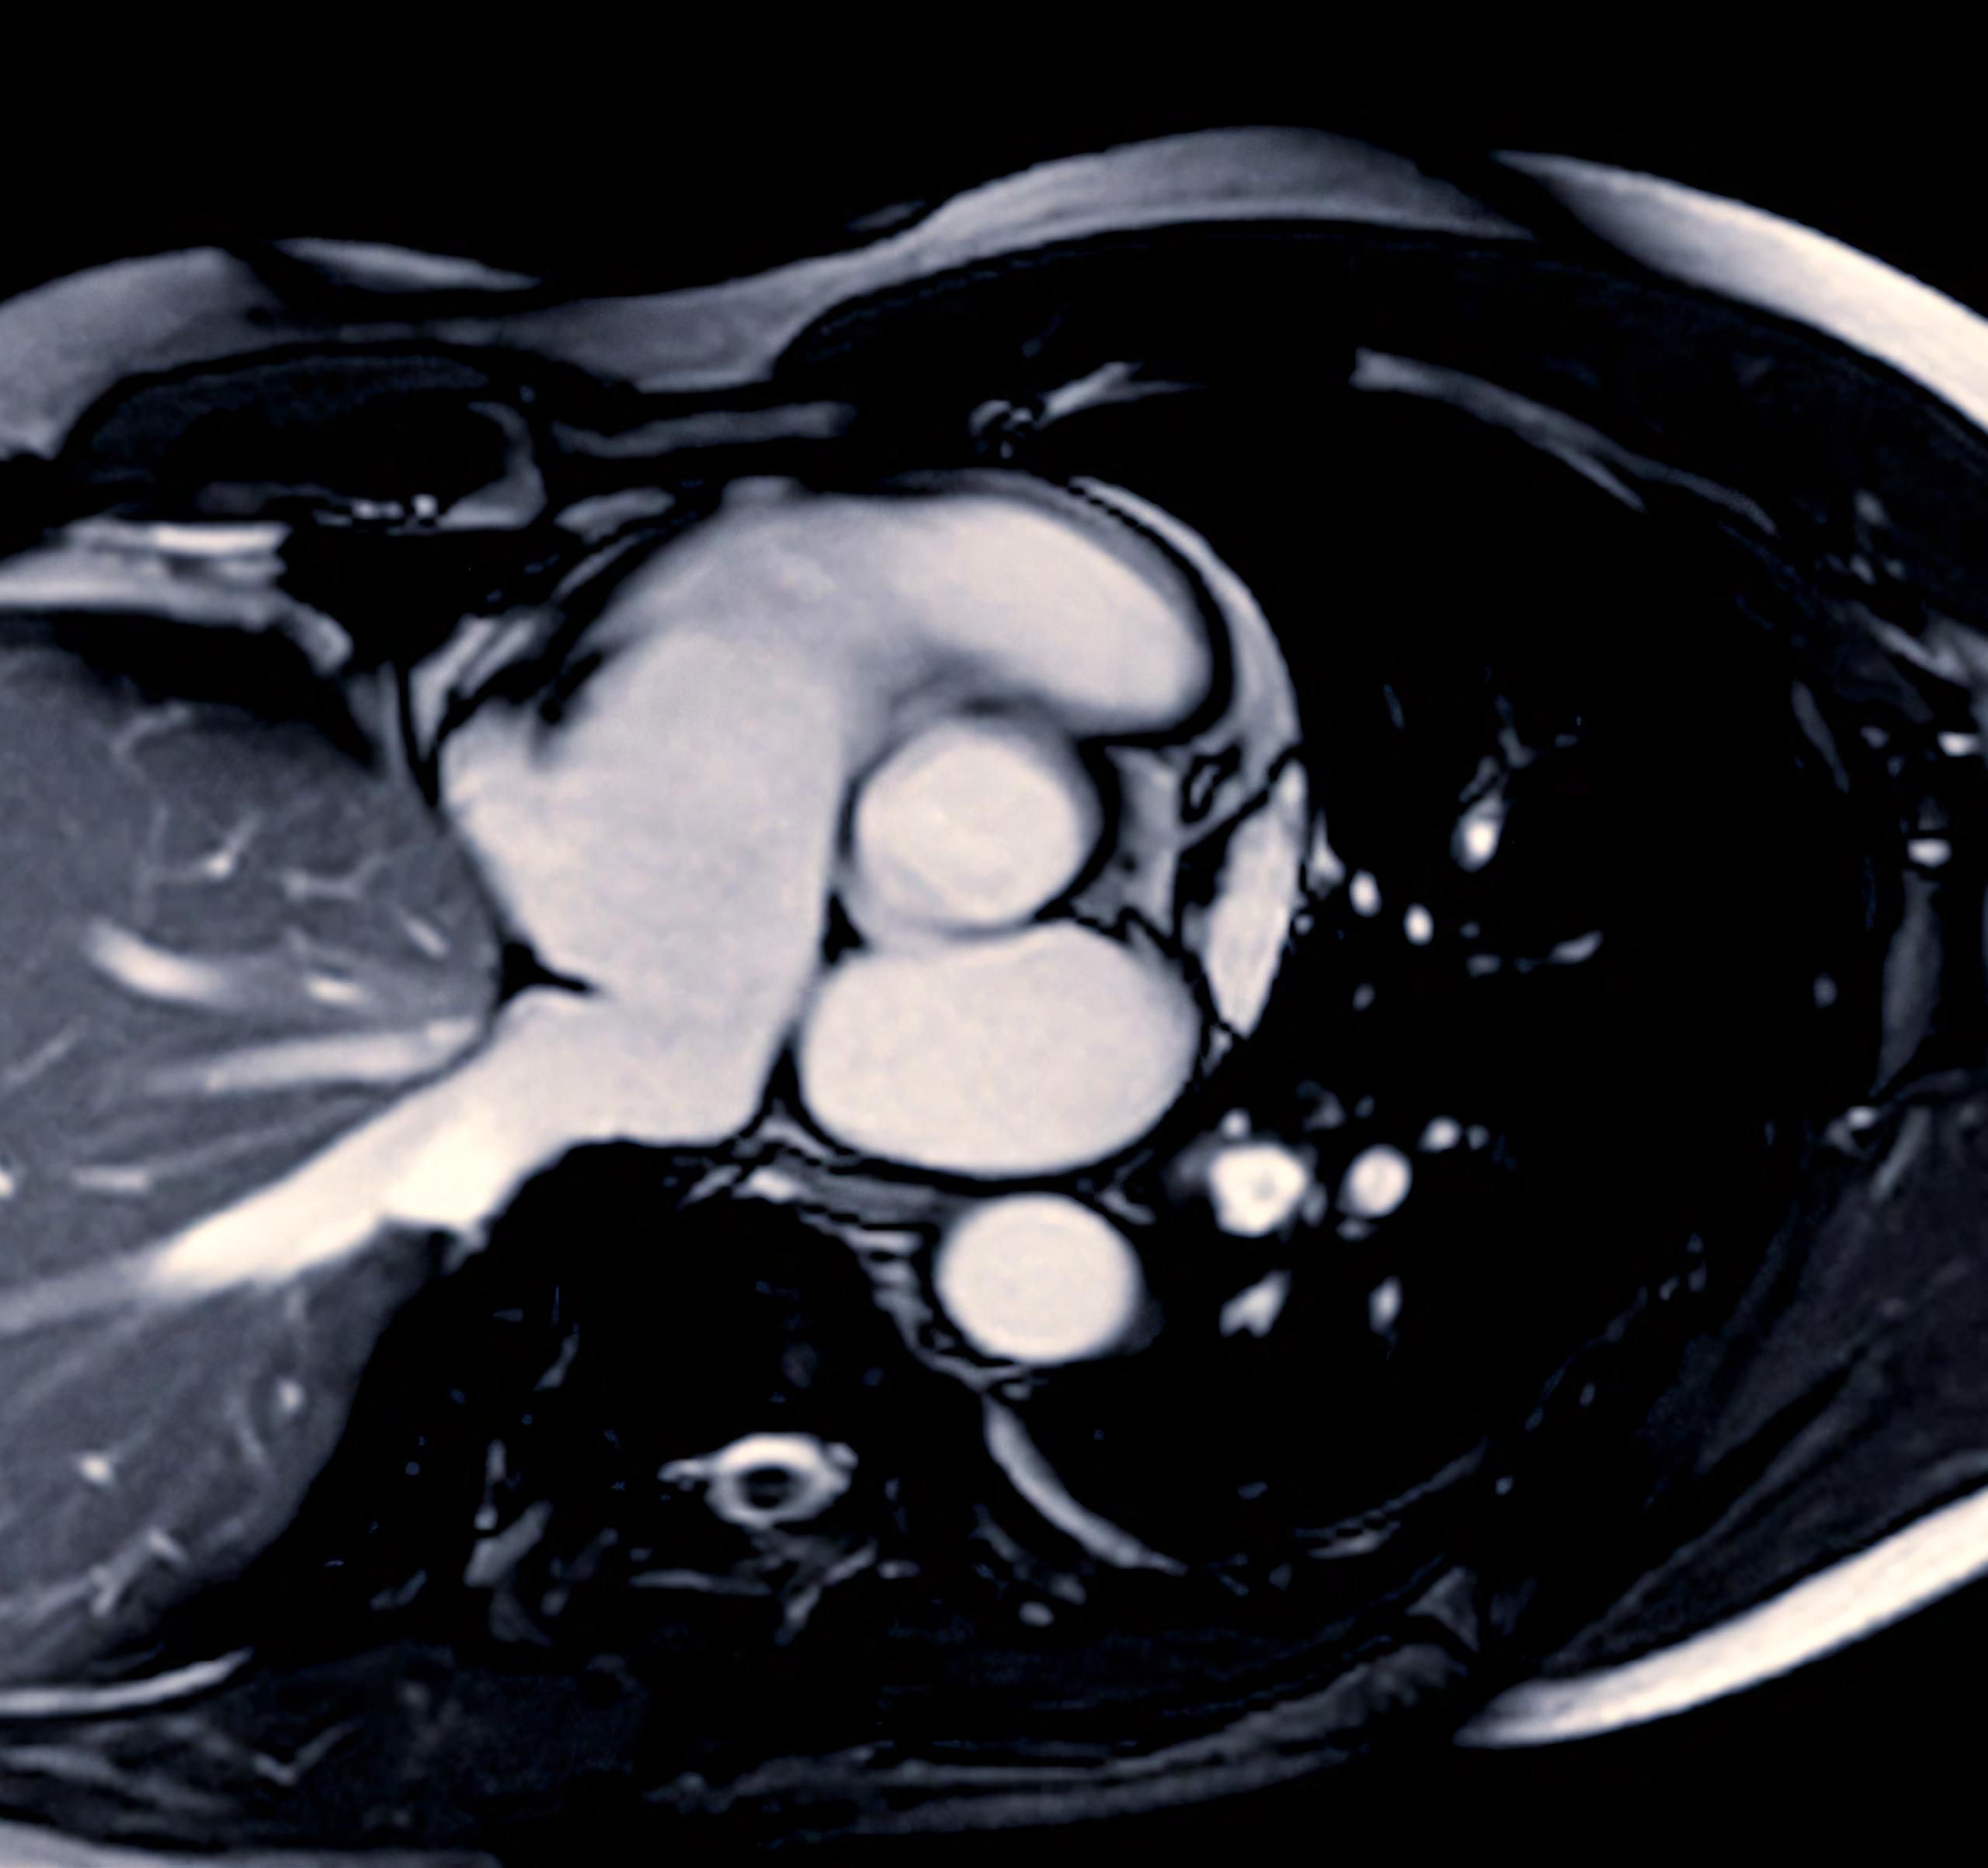

David Nordsletten, U-M Professor, Biomedical Engineering and Cardiac Surgery, along with Ralph Sinkus, INSERM and King’s College London, Chair and Professor, Biomedical Engineering and Research Director of CNRS/France, Paris, present a novel scattering theory, in conjunction with MRI-based elastography imaging, which enables the unraveling of a material’s innate constitutive and scattering characteristics. By overcoming a three-order-of-magnitude scale difference between wavelength and average inter-vessel distance, they demonstrate non-invasively a macroscopic measure of vascular architecture.

Drs. Nordsletten and Sinkus explained that researchers can see waves inside an object using similar wave technology. The technology is based on seeing waves inside the object via MRI, where external vibrations are transmitted through the

body to show their spatial organization as they traverse organs and tissues. From these waves, it is possible to analyze the physics.

Cardiac MRI images are instrumental in assessing cardiac health, identifying heart abnormalities, and guiding treatment plans.

- David Nordsletten, Professor, Biomedical Engineering and Cardiac Surgery